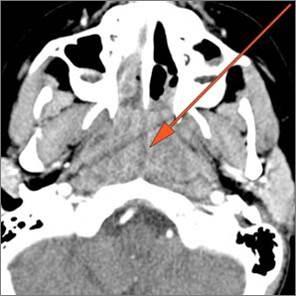

9 month old male presenting to the emergency room with poor feeding, fever, respiratory distress and possible retropharyngeal abscess or suppurative retropharyngeal adenitis.Exam

There is reactive retropharyngeal lymphadenopathy. |

There is suppurative retropharyngeal lymphadenopathy. |

Yes | NA |

If there is suppurative retropharyngeal adenopathy what is the maximum short axis dimension of the largest suppurative node. Measurement |

< 2cm | NA |

There is edema/abscess within the adjacent parapharyngeal and retropharyngeal spaces. |

There is edema/abscess within in the prevertebral or paravertebral spaces. |

Pharyngitis with suppurative retropharyngeal adenitis.